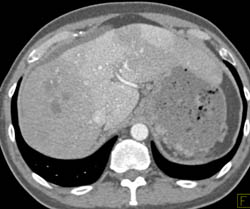

Hepatoma in Caudate Lobe With Cirrhosis